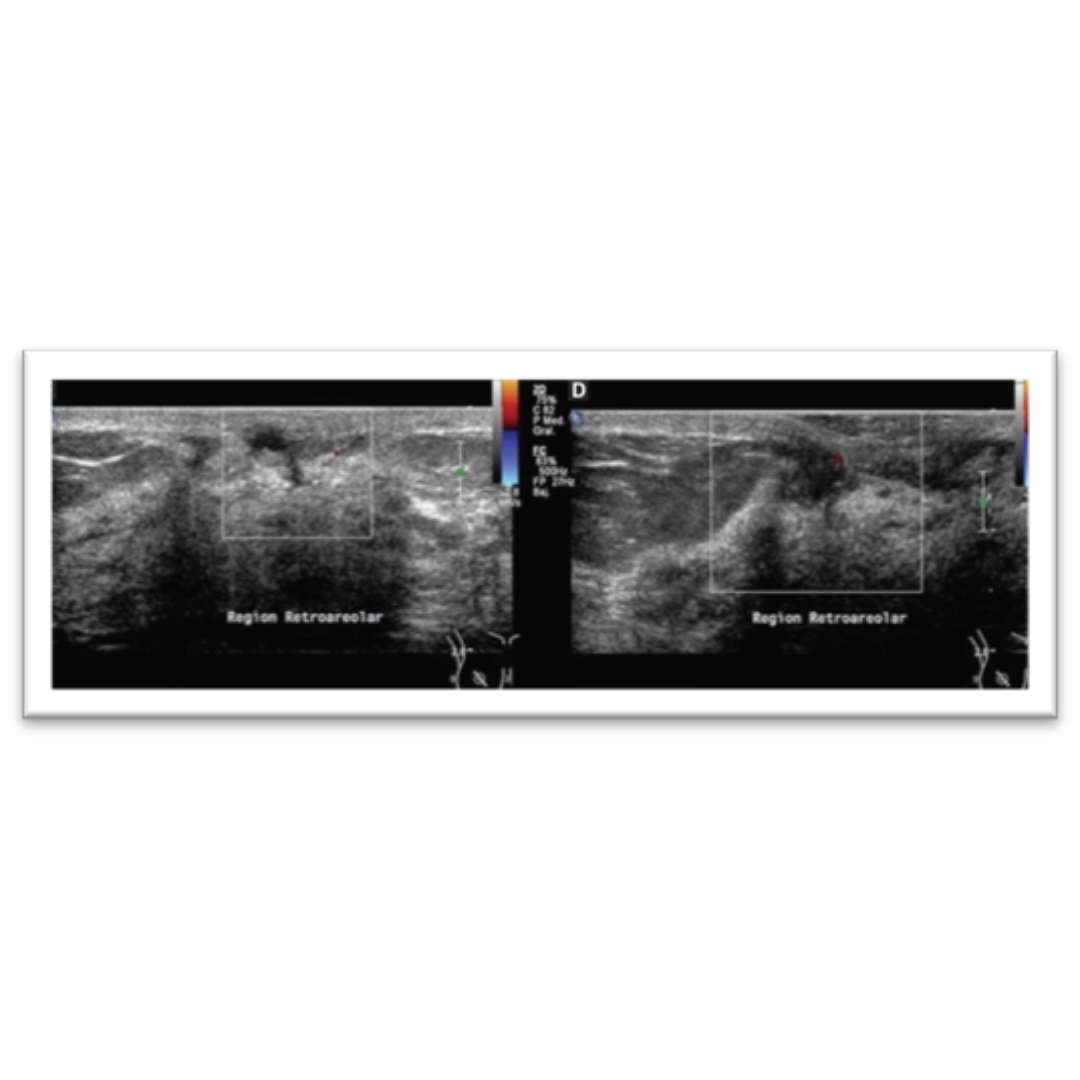

Imagen 2: Se observan en la región retroareolar derecha dos nódulos sólidos intraductales de 2 y 6 mm, que muestran vascularidad periférica a la aplicación Doppler color.

Se origina en los ductos del pezón y se manifiesta por telorrea, prurito, eritema, erosión o nodularidad, puede ser asintomático también.

• Al US: masa lobulada u oval, homogénea, iso o hipoecogénica en el pezón, con incremento en la vascularidad en Doppler.

• DD: carcinoma ductal, en casos sospechosos se realiza biopsia para determinar atipia de la lesión.